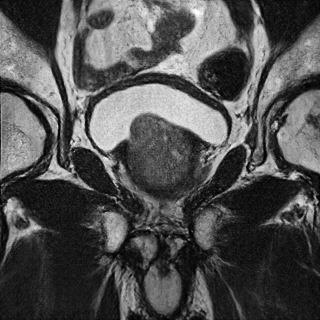

Refer to caption

(a) Ground Truth

(b) Low resolution input

(c) Proposed SR Result

Figure 1: Example of Data and Proposed Result

We first convert the DICOM format of the input images to PNG to make them compatible with our models and resize the images so that the random cropping function, which produces 224×224224224224\times 224 crops, works correctly. We additionally scale the images so that the pixel values range from -1 to 1. An example of the data and proposed SR solution is shown in Fig. 1. We run all of the ML SR techniques on Google Cloud using an NVIDIA Tesla K80 GPU to accelerate training.